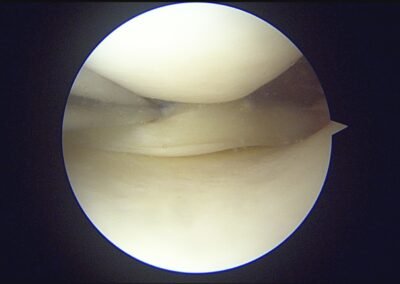

GalleryShoulder rotator cuff repair Meniscus root repair Meniscus repair Bankart repair for recurrent shoulder dislocation ACL reconstruction Machines Instruments